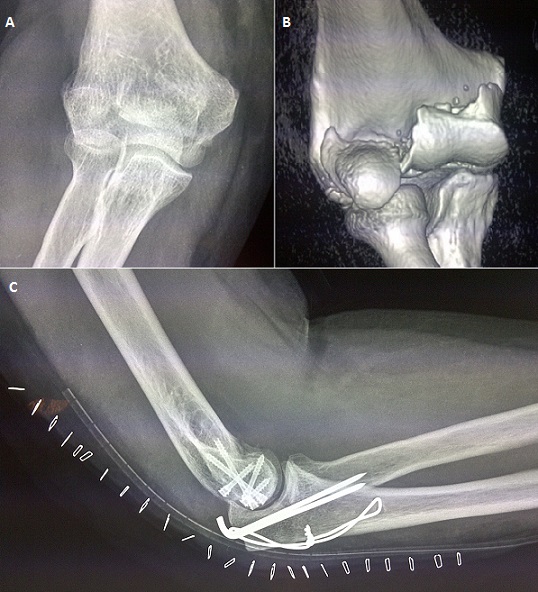

Les fractures articulaires frontales de l'épiphyse distale de l'humérus sont souvent désignées par le terme vague de fractures du capitellum. Ce sont des fractures rares; elles représententprès de 13 % des fractures de cette extrémité osseuse. Parmi ces types fracturaires, la fracture diacondylienne ou fracture de Kocher-Lorenz représente une variété encore plus rare. Nous rapportons le cas d'un patient de 30 ans victime d'une chute directe sur le coude droit en flexion. Le patient s'est présentée aux urgences pour douleur et impotence fonctionnelle. La radiographie du coude (A) a objectivé une fracture diacondylienne avec trait de fracture séparant la trochlée et le condyle sans lésions associées. Une TDM (B) a été demandée pour une meilleure étude de la fracture avant ostéosynthèse. Elle permet également d'éliminer les autres diagnostics différentiels qui sont d'autres lésions à traits de fractures frontales, celle du capitellum, de Hahn Steinthal ou bien les fractures diacolumnaires. Nous avons eu recours à une voie d'abord postérieure avec ostéotomie de l'olécrane avec fixation interne par trois vis antéro postérieure et deux vis obliques. Les pas de vis ont été enfouis de telle sorte qu'ils ne soient plus proéminents dans l'articulation. Une radiographie de contrôle a été réalisée (C). La rééducation a été commencée une semaine après l'intervention. L'évaluation clinique a été réalisée après 5 ans de recul selon l'index de performance du coude décrit par Morrey et al, le résultat a été jugé excellent avec un score de 91 sur 100.